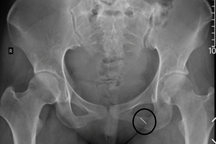

Viên thuốc còn nguyên vỏ có kích thước 2x2cm (Ảnh: H.T.).

Các bác sĩ Khoa Nội tổng hợp đã tiến hành nội soi dạ dày và gắp dị vật là một viên thuốc còn nguyên vỏ, kích thước 2x2cm nằm tại vị trí giữa lỗ môn vị và tá tràng.